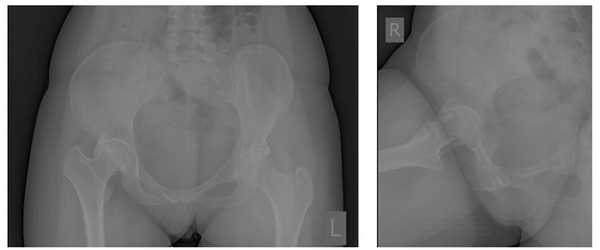

Пациент П. 64 лет на протяжении 3 лет отмечает выраженные, постепенно прогрессирующие боли в области правого тазобедренного сустава. Обратился в К+31 в мае 2017, осмотрен ортопедом, выполнены рентгенограммы тазобедренных суставов. Диагностирован коксартроз справа 3 ст, слева 2 ст. Рекомендовано оперативное лечение - тотальное эндопротезирование правого тазобедренного сустава.

Учитывая возраст пациента решено использовать протез бесцементной фиксации фирмы Zimmer, пара трения керамика\керамика.

Произведено предоперационное планирование, рассчётные размеры: ножка Avenir 6, чаша Trilogy 60, керамический вкладыш с внутренним диаметром 40 мм, керамическая головка 40 мм.

Пациент К. 68 лет, на протяжении 1 года отмечал постепенное нарастание болей и ограничение амплитуды движений в правом тазобедренном суставе. Обратился в К+31 в августе 2017 года, при выполнении рентгенографии выявлен асептический некроз головки правого бедра, коксартроз 3 стадии.

Пациентка Ж, 28 лет. Обратилась в К+31 в октябре 2017. Страдала врождённым подвывихом головки правого бедра, лечение в детсве не проводилось (на тот момент рутинного УЗИ скрининга в СССР не было, а к детскому ортопеду направляли не всех детей). В возрасте 23 лет отметила появление болей в области правого тазобедренного сустава. На протяжении последних 3 лет отмечала нарастание болевого синдрома, нарушение походки, ограничение амплитуды движений и постепенное укорочение конечности. Обратилась в К+31, выполнены рентгенограммы на которых визуализируется коксартроз 3 ст справа на фоне дисплазии правого тазобедренного сустава.

Снимки после операции. Длина конечности восстановлена. В сравнении со снимками до операции хорошо видно как восстановилось нормальное положение тазового кольца и поясничного отдела позвоночника. Пациентка была прооперирована в день поступления, переведена из РАО через 2 часа после операции, активизирована через 6 часов после операции. На вторые сутки обучена ходьбе с дополнительной опорой на костыли.